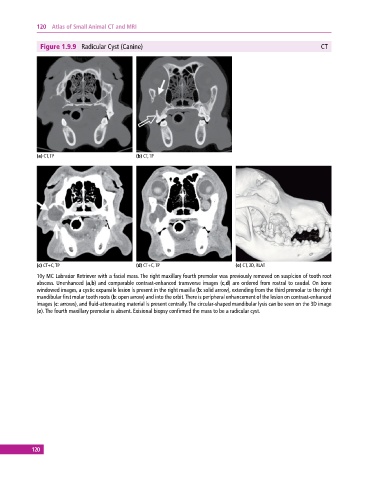

Figure 1.9.9 Radicular Cyst (Canine) CT

(a) CT, TP (b) CT, TP

(c) CT+C, TP (d) CT+C, TP (e) CT, 3D, RLAT

10y MC Labrador Retriever with a facial mass. The right maxillary fourth premolar was previously removed on suspicion of tooth root

abscess. Unenhanced (a,b) and comparable contrastenhanced transverse images (c,d) are ordered from rostral to caudal. On bone

windowed images, a cystic expansile lesion is present in the right maxilla (b: solid arrow), extending from the third premolar to the right

mandibular first molar tooth roots (b: open arrow) and into the orbit. There is peripheral enhancement of the lesion on contrastenhanced

images (c: arrows), and fluid‐attenuating material is present centrally. The circular‐shaped mandibular lysis can be seen on the 3D image

(e). The fourth maxillary premolar is absent. Exisional biopsy confirmed the mass to be a radicular cyst.